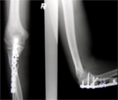

Infected Non-Union Ulna

28 years old male with infected non-union ulna

Open fracture Grade1 treated with debridement and plating. Resulted in infected non-union with bone loss. External fixator and bone excision done

Wide bone excision of infected bone, Ilizarov fixator appplication and corticotomy done

Docking of bone seen on serila Xrays and regenerate forming at bone transport site

Healing of non-union with intramedullary rod (to facilitate early fixator removal) and artificial bone graft at docking site. Good union and return of elbow motion